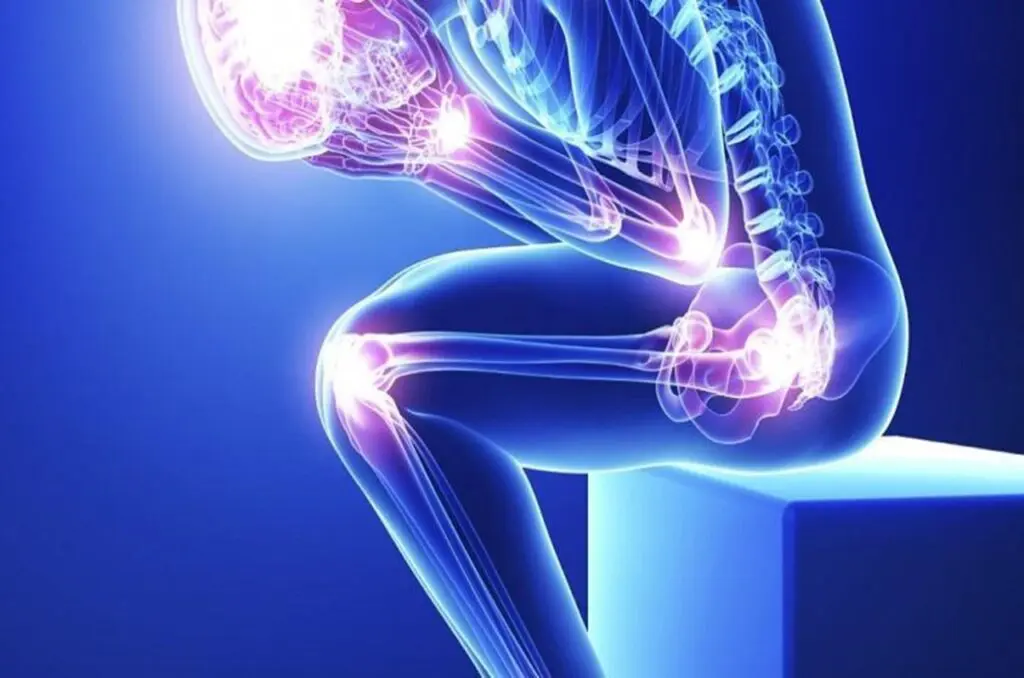

A síndrome da fibromialgia (FM) é uma síndrome clínica que se manifesta com dor no corpo todo, principalmente na musculatura. Junto com a dor, a fibromialgia cursa com sintomas de fadiga (cansaço), sono não reparador (a pessoa acorda cansada) e outros sintomas como alterações de memória e atenção, ansiedade, depressão e alterações intestinais. Uma característica da pessoa com FM é a grande sensibilidade ao toque e à compressão da musculatura pelo examinador ou por outras pessoas.

De cada 10 pacientes com fibromialgia, sete a nove são mulheres. Não se sabe a razão porque isto acontece. Não parece haver uma relação com hormônios, pois a fibromialgia afeta as mulheres tanto antes quanto depois da menopausa. Talvez os critérios utilizados hoje no diagnóstico da FM tendam a incluir mais mulheres. A idade de aparecimento da fibromialgia é geralmente entre os 30 e 60 anos. Porém, existem casos em pessoas mais velhas e também em crianças e adolescentes.